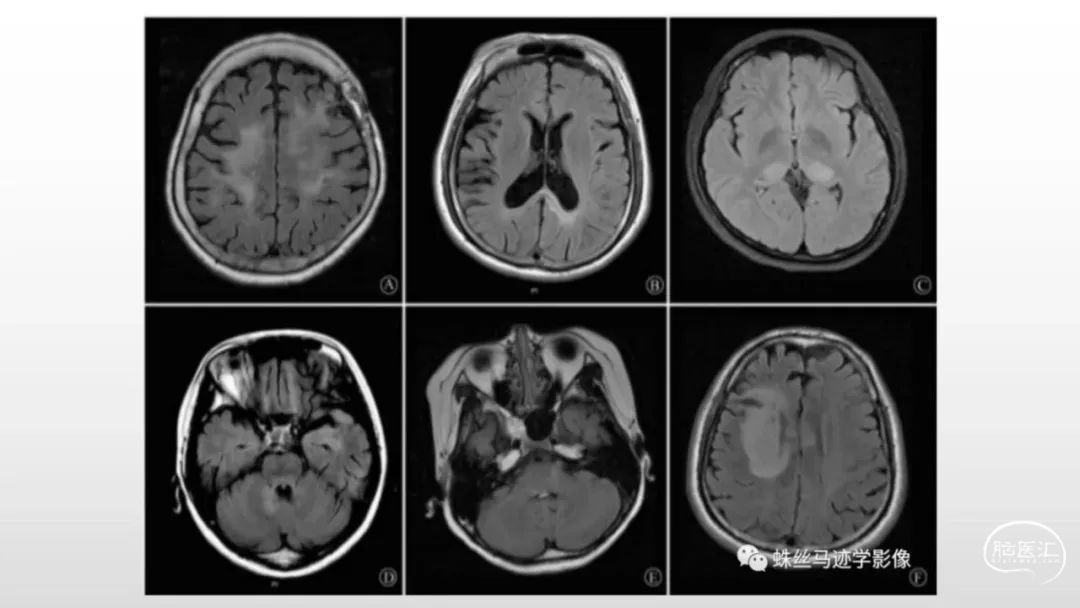

颅脑影像诊断基础知识讲座:感染和免疫性疾病2